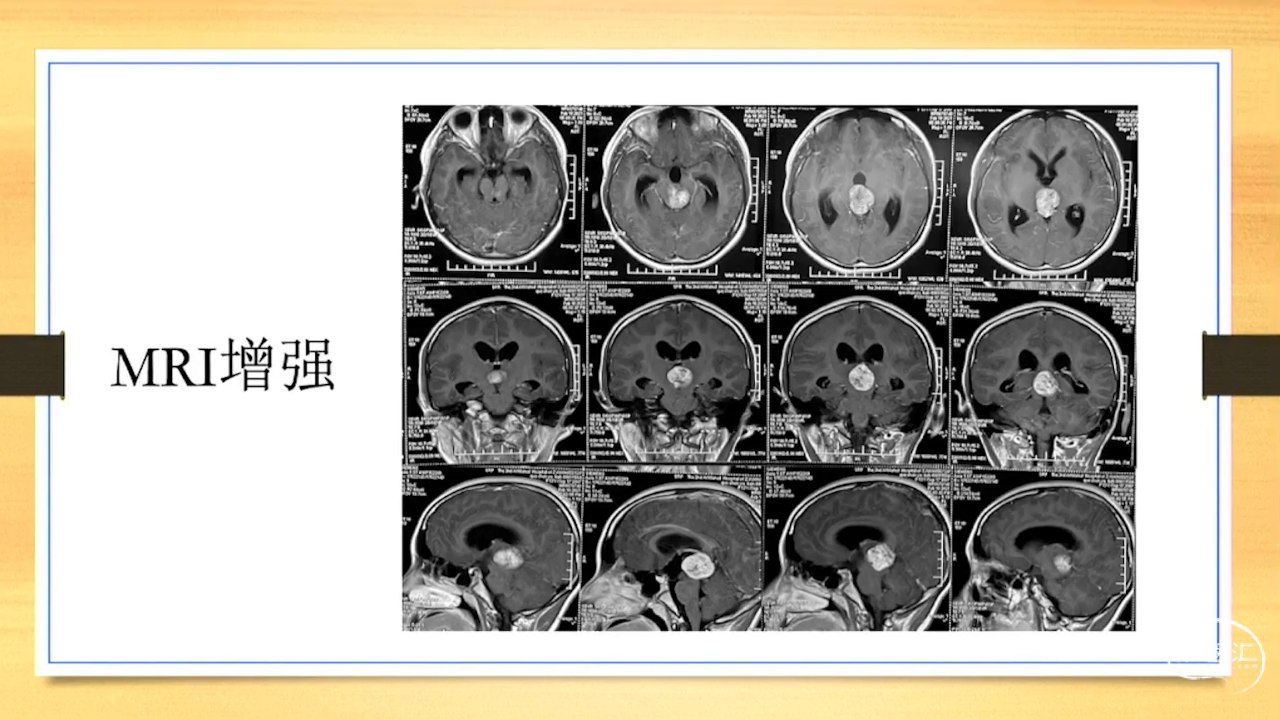

张荣教授:儿童颅内生殖细胞瘤的手术治疗

颅内生殖细胞肿瘤的治疗是手术、放疗、化疗、内分泌及其他多学科的整合治疗。及时、精准、合理的手术治疗是iGCT患者提高生存率、降低并发症、改善神经内分泌功能的关键。